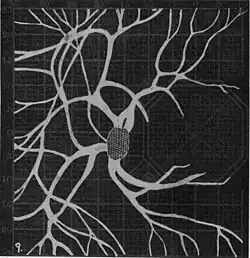

Angioscotomas were first discovered and mapped out by John Norris Evans (1891-02-28--1953-04-08)[2] in 1926, who coined the term angioscotometry to describe the painstaking charting of the scotoma of the retinal blood vessels by manual perimetry. He seated each subject in a seat in a dark setting, and tested whether they could see a tiny bright test object placed at various locations.[3] Using a 1.5 mm white disk, Evans reported intricate branch‑like scotomas that mirrored the arteries and veins emerging from the optic disc, with a full map requiring up to 2 hours to complete. He plotted this for subjects under various conditions, such as while holding breath, with glaucoma, etc. A year later, he confirmed that only short stump‑like scotomas had been noticed previously, some further data plotted with a smaller 1 mm stimuli, and under varying conditions on the subject.[4] He published a monograph on this in 1938 in which he described its use in assisting diagnosis of various conditions, such as retinal edema, glaucoma, optic neuritis, etc.[5]

Using eccentric fixation, the more nasal parts of the angioscotoma can be plotted. -

1. Pressure on globe shows only stumps of large vessels. 2. Holding the breath causes similar effect; also 3. Holding the head low. 4. Pressure on opposite eye widens arteries and still more veins, 5. Pressure on the carotid produces no definite effect. 6. Looking thru red glass brings out finer vessels. -

Widening of angioscotoma under various conditions (holding head lower than trunk; holding the breath; making digital pressure on the same eye; (a vein) on opposite eye; (an artery) on opposite eye).